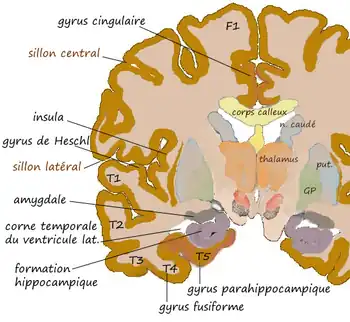

L'amygdale ou complexe amygdalien est un noyau pair situé dans la région antéro-interne du lobe temporal au sein de l'uncus, en avant de l'hippocampe et sous le cortex péri-amygdalien.

Coupe coronale au niveau de l'amygdale. |